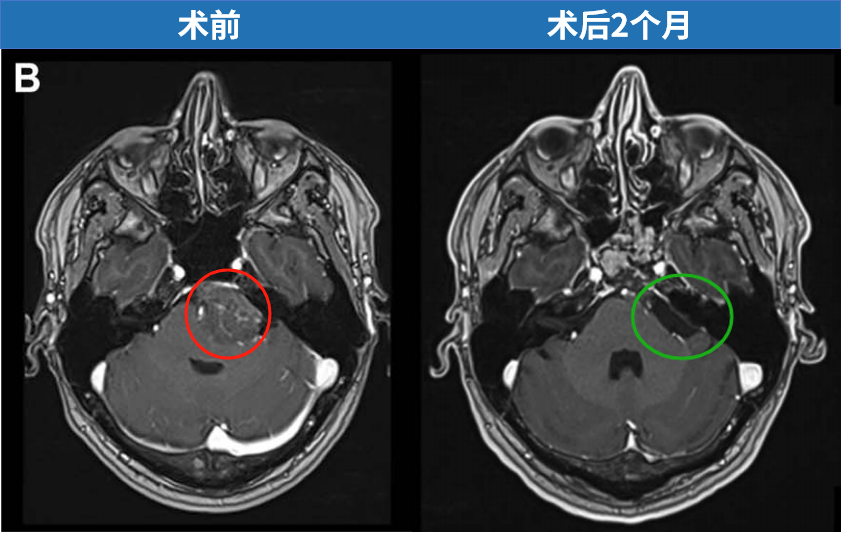

福教授采用开颅手术,术前通过线圈在咽升动脉处进行栓塞,可以显著减少术中出血。在切除肿瘤过程中,使用CUSA刀对肿瘤逐渐减瘤。术后MRI显示肿瘤几乎完全切除,脑干受压解除。